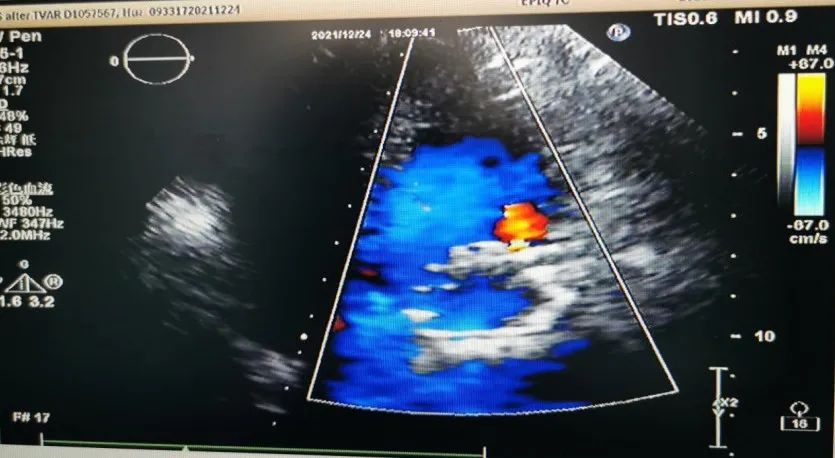

术后及术后超声: